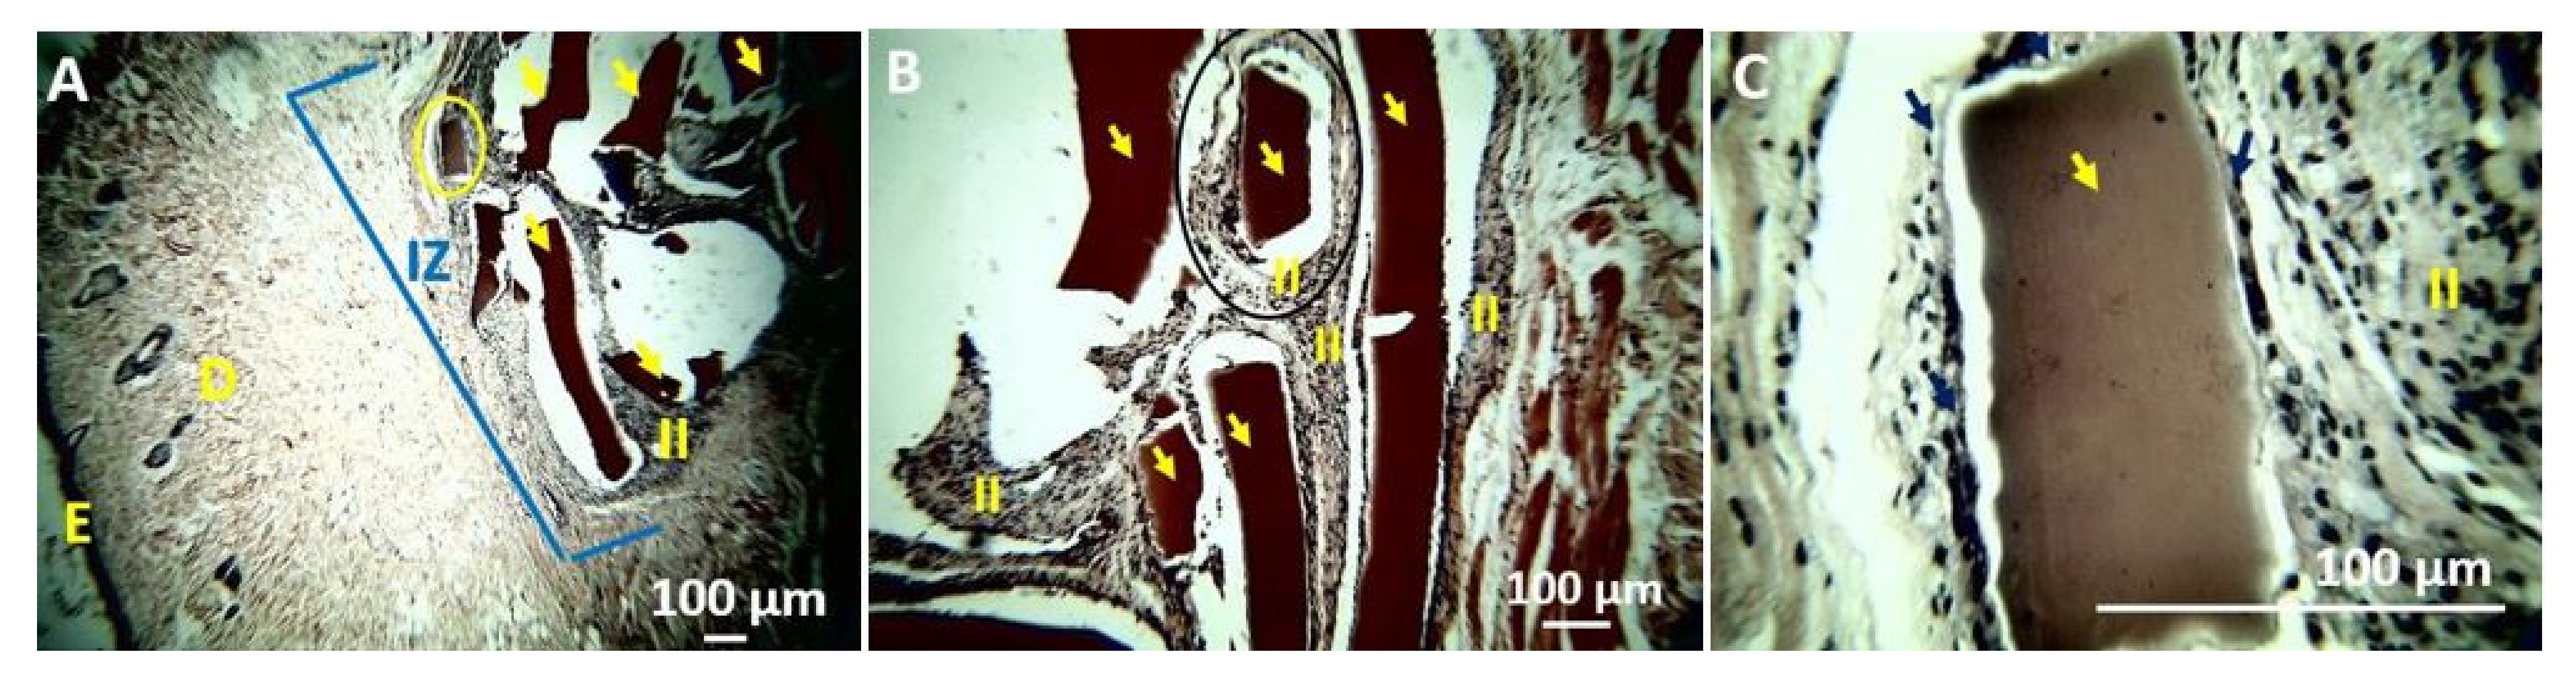

4. In Vivo Biocompatibility Tests of the CS/PVA/TTEO Films